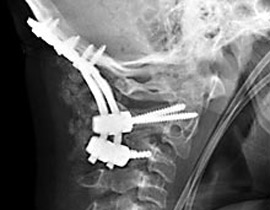

وعقب حصول الحادث في أواخر العام 2006، قام الأطباء بإخضاع الصبي المصاب إلى عملية جراحية عاجلة استمرت لمدة 7 ساعات، وهي العملية التي نجحوا خلالها في إعادة تثبيت فقرات رقبته وتوصيلها إلى قاعدة الجمجمة باستخدام مسامير وشرائح مصنوعة من معدن التيتانيوم.

وقال الأطباء أن أفضل ما كانوا يتوقعونه هو أن يبقى الصبي على قيد الحياة، لكن حالته شهدت تحسنا ملموسا واستمر في التعافي من إصابته بشكل مذهل إلى أن عاد أخيرا إلى مزاولة رياضة سباقات السيارات.